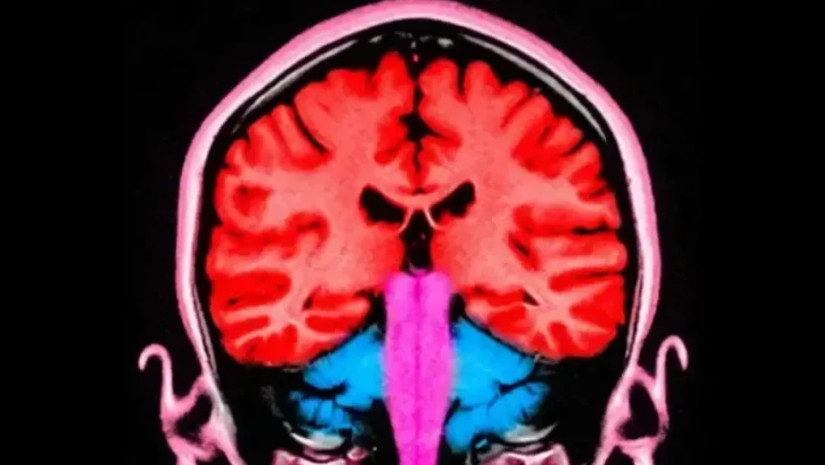

მონაწილეები გადაწყვეტილების მიღების პროცესში ტვინის შუბლისა და პარიეტალურ რეგიონებში სუსტი ინტენსივობის ელექტრულ სტიმულაციას იღებდნენ — ეს უბნები ტვინის წინა და უკანა ნაწილებში მდებარეობს და გადაწყვეტილებების მიღებასთან, სოციალური ქცევისა და ემპათიის რეგულაციასთანაა დაკავშირებული.

ჟურნალ PLoS Biology-ში გამოქვეყნებული ახალი აღმოჩენა წინა კვლევას ეყრდნობა - იმ ექსპერიმენტში მკვლევრებმა დააფიქსირეს ტვინის ორი რეგიონი, რომლებიც, როგორც ჩანს, ერთმანეთთან კოორდინირებულად მუშაობდნენ — მათი ნეირონული აქტივობა ერთსა და იმავე რიტმსა და სიხშირეს მიჰყვებოდა.

ამჯერად მკვლევრებს სურდათ დაედგინათ, შესაძლებელი იყო თუ არა ამ ორი რეგიონის კოორდინირებული მუშაობის ხელოვნურად გაძლიერება — და, შედეგად, ადამიანების უფრო უანგარო არჩევანისკენ "ბიძგი".